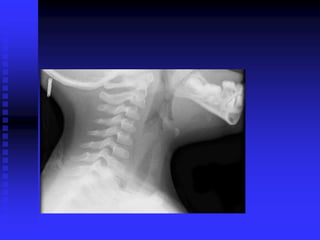

Epiglottitis: Signs/Symptoms

 Rapid onset, severe distress in hours

 High fever

 Intense sore throat, difficulty swallowing

 Drooling

 Stridor

 Sits up, leans forward, extends neck slightly

 One-third present unconscious, in shock